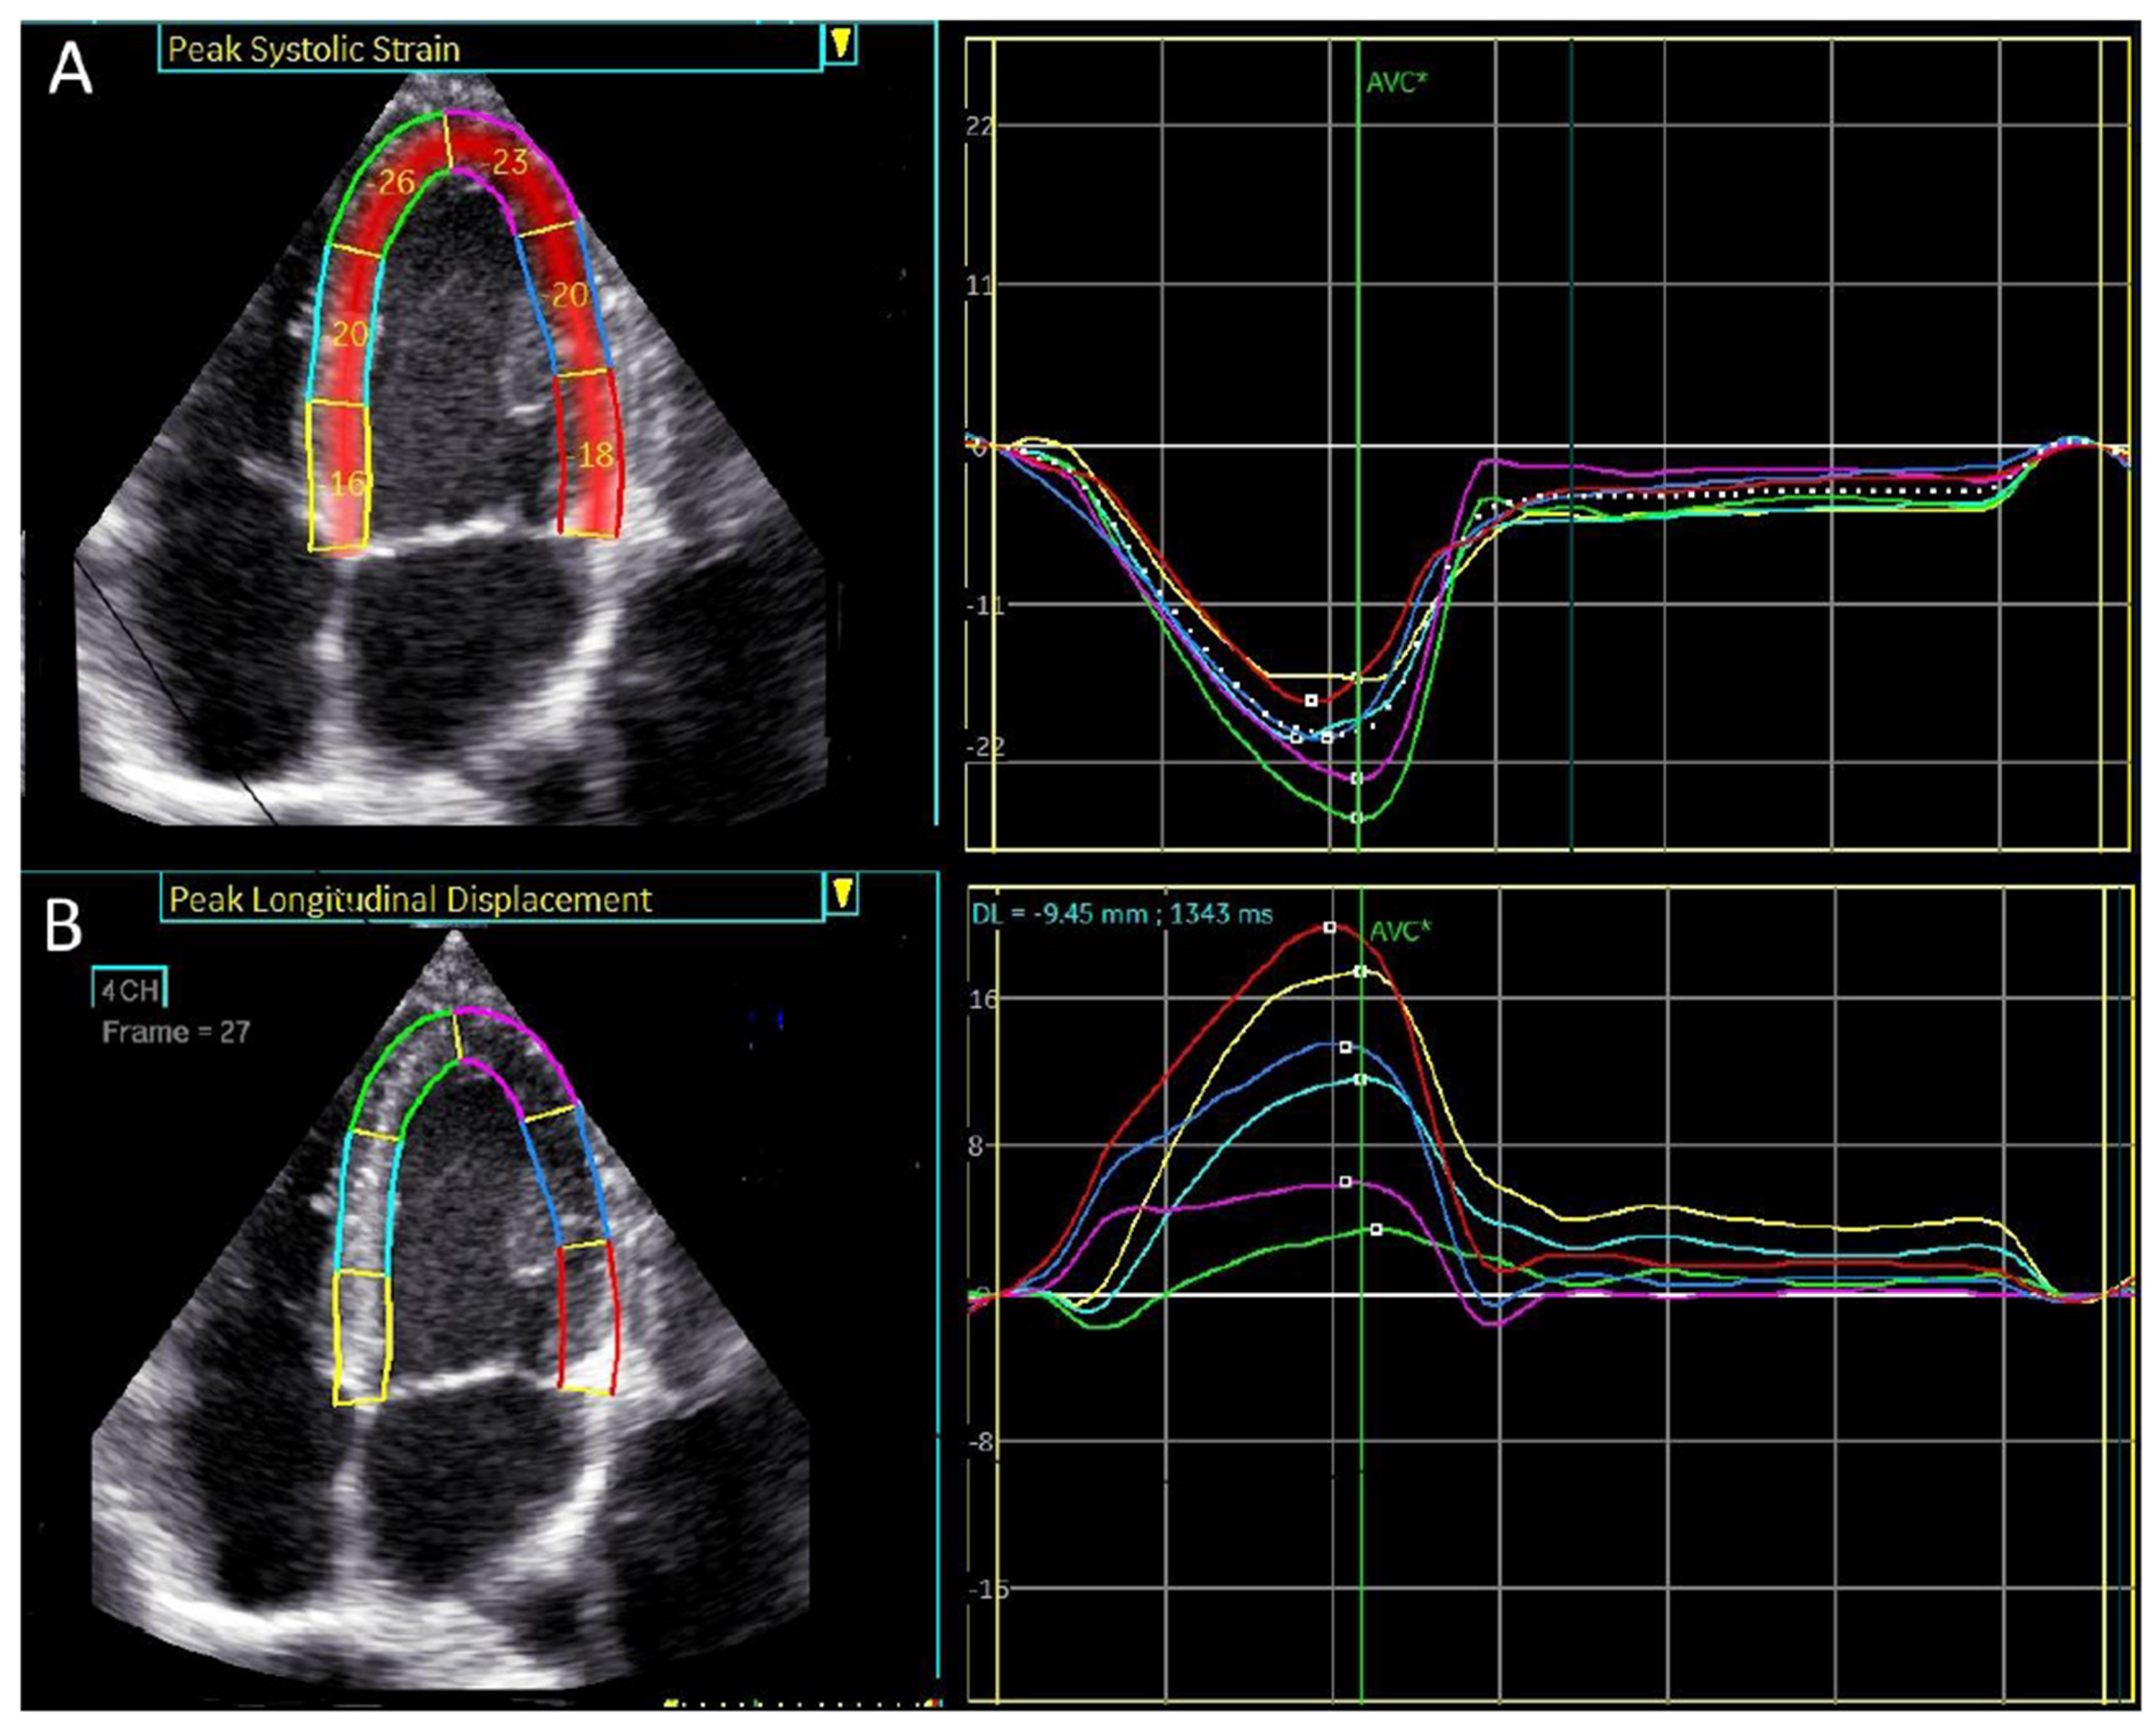

An example of peak systolic regional longitudinal displacement and strain for a 27-year-old football player is shown in Figure 5A,B. In contrast to the peak systolic strain, which exhibits a basal-to-apical gradient, peak longitudinal displacement is highest in the basal segments and lowest in the apical segments, demonstrating a reversed basal-to-apical gradient.

Figure 5.

A visual plot of the normal peak longitudinal displacement and strain of 27-year-old football player. (A) Peak longitudinal displacement is highest in the basal segments and lowest in the apex. (B) Peak longitudinal strain is lowest in the basal segment and highest in the apex.